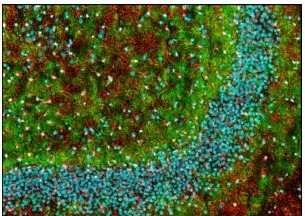

This Anti-Myelin Basic Protein Mouse mAb (SMI-99) is validated for use in ELISA, Immunoblotting, Immunocytochemistry, Frozen Sections, Paraffin Sections for the detection of Myelin Basic Protein.

More>> This Anti-Myelin Basic Protein Mouse mAb (SMI-99) is validated for use in ELISA, Immunoblotting, Immunocytochemistry, Frozen Sections, Paraffin Sections for the detection of Myelin Basic Protein. Less<<Empfohlene Produkte

| Positive control | Rat brain |